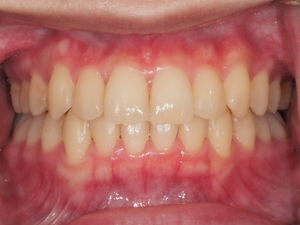

ガタガタとした歯並びや八重歯(叢生)CASE63